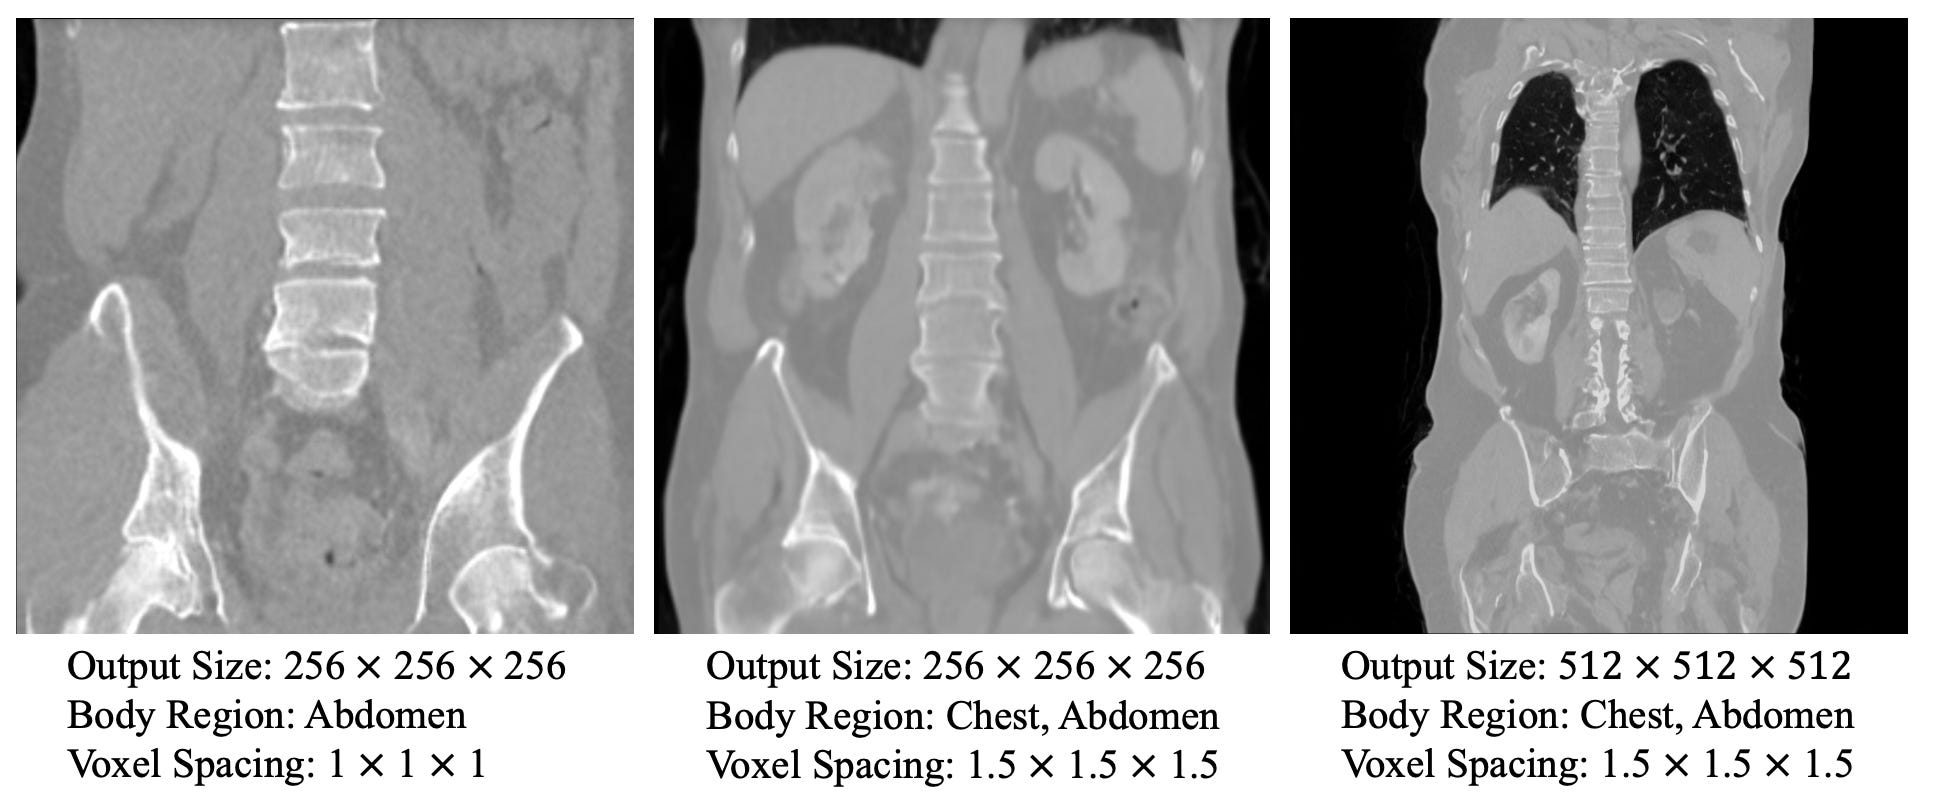

MAISI - Synthetic Medical Imaging 🫁

One of the main the limitations for training models is data accessibility. There is never enough data. This year we have witnessed a lot of models and tools to generate data across different domains. Today we introduce MAISI, the latest tool from the Medical Open Network for Artificial Intelligence, a project started by NVIDIA and King's College London. MAISI can generate realistic large CT images accompanied by corresponding segmentation masks.

📌 Key Insights:

127+ different anatomies supported

Generating both CT and MRI scans with flexible volume size and voxel size

Large image generation - up to 512 × 512 × 768 size